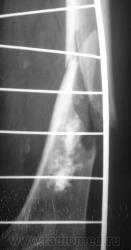

Ну, и, после "репозиции".

После репозиции дистальный отломок смещён латерально на ширину кортикального слоя.

Что это - не скажу (под рукой нет литературы). Но. 1.Процесс опухолевый - в средней части, по заднему контуру отмечается вздутие кости. 2.Относительно длительно текущий - вздутие достаточно протяженное. 3.Пока еще относительно доброкачественный - кортикальный слой созранен. 4. Многоузловой (мультифокальный) - не менее 3-х узлов/фокусов. В зависимости от возраста/пола/анамнеза вполне может быть метастатическим. 5.Перелом все-таки патологический - линия перелома проходит через верхнюю часть патологического субстрата.

Это может оказаться и безобидным обызвествлением костного мозга после инфаркта, хондромой или хондросаркомой. - Уроки Татьяны Валентиновны. Но вздутия не вижу - его в боковой проекции симулирует третий фрагмент в месте перелома. Ну а метастаз - маловероятен... Опять же - "горим" на сочетанной патологии...

хочу поддержать доктора Анатолия Шумакова: перелом вряд ли патологический, обызвествление костного мозга бедренной кости и вероятно стенок сосудов